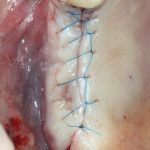

Наложение швов.

Если на этапе разреза и формирования раны всё сделано правильно, то наложение швов не вызывает особых трудностей. Периостотомия или послабляющие разрезы на периосте не требуются (ни практически никогда не требуются). А сами швы получаются аккуратными и герметичными:

Обрати внимание, что все шовные лигатуры находятся в пределах кератинизированной десны. Это позволяет избежать деформации тканей и лишних рубцов. В наиболее уязвимых местах (около зубов) шовные лигатуры лучше продублировать.

Если бы мне пришлось делать это сейчас, то я бы использовал непрерывный «матрацный» шов. Он удобнее, быстрее в наложении и комфортнее для пациента. Минус — если распускается, то распускается весь. К тому же, его очень неудобно снимать.

Несмотря на то, что уже тогда мы широко использовали непрерывные швы в подобных случаях, здесь я, во-первых, зассал (может распуститься), во-вторых, снятие швов предполагалось в поликлинике по месту жительства пациентки, и мне не хотелось, чтобы там при снятии швов начудили. Как выяснится позже — зря беспокоился.

Неизменно одно — в таких операциях мы использовали и до сих пор используем нерезорбируемые монофиламентные шовные материалы, поскольку они наиболее гигиеничные. Чтобы острые концы нитей не беспокоили пациента, их можно оплавить нагретой гладилкой или гуттаперчевым плаггером.